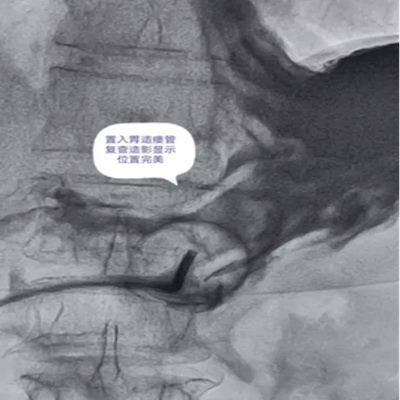

DSA引导下经皮胃造瘘术,是在数字减影血管造影(DSA)这个“透视眼”的实时可视化导航下,于患者腹壁上建立一个仅 3-5毫米 的微小穿刺点。通过这个“针眼”,医生精准地将一根营养管直接置入胃部,建立起一条直达的营养通道。

整个过程就像一次精准的“导航穿刺”,全程操作便捷、创伤小,却能完美替代传统的鼻饲管,为患者提供长期、稳定、安全的营养支持。

DSA影像全程清晰可视化,可精准避开血管、脏器等重要组织,穿刺定位误差小;穿刺创口仅3-5mm,出血量少,术后反流、误吸、肺炎等并发症发生率低于5%,术后1-2天即可正常喂养,恢复速度快。